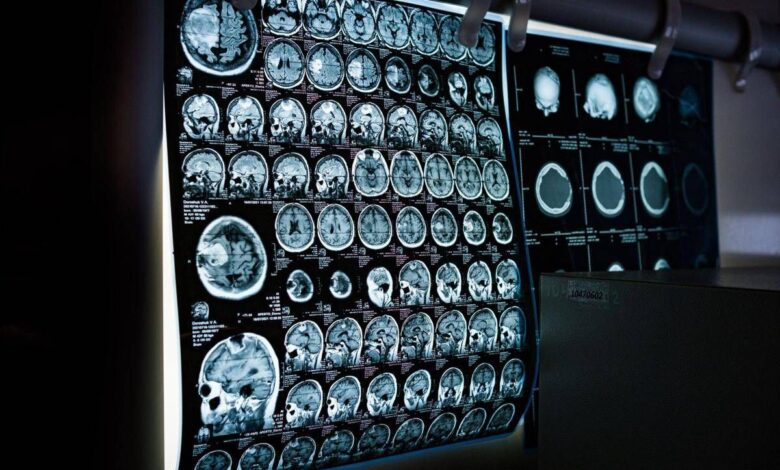

Uno spray nasale testato sui modelli animali potrebbe invertire l’invecchiamento del cervello con sole 2 dosi, riducendo drasticamente l’infiammazione cerebrale, ripristinando le centrali energetiche cellulari del cervello e migliorando così significativamente la memoria. Un processo di ringiovanimento che agirebbe nel giro di poche settimane per durare mesi.

E’ il risultato dello studio condotto dai ricercatori della Texas A&M University (Naresh K. Vashisht College of Medicine) negli Stati Uniti. Lo spray contiene minuscole particelle biologiche note come vescicole extracellulari (Ev), che agiscono come veicoli di consegna con a bordo un potente carico genetico, i microRna. Le sostanze aggirano lo scudo protettivo del cervello e viaggiano direttamente nel tessuto cerebrale, dove vengono assorbite. Arrivati a destinazione nelle cellule immunitarie residenti nel cervello, i microRna ‘spengono’ i sistemi noti per essere responsabili dell’infiammazione cronica nel cervello che invecchia.

Per spiegare il senso di questo processo, gli scienziati invitano a immaginare il cervello come un motore ad alte prestazioni: nel corso dei decenni questo motore non solo si usura, ma inizia anche a surriscaldarsi. Piccoli ‘focolai’ di infiammazione covano nelle profondità del centro della memoria, creando una persistente nebbia mentale (brain fog) che rende più difficile pensare, formare nuovi ricordi o persino adattarsi a nuovi ambienti, aumentando al contempo il rischio di disturbi come il morbo di Alzheimer. Questo processo a lenta combustione viene chiamato neuroinfiammazione. E per decenni si è pensato che fosse il prezzo inevitabile dell’invecchiamento. Ma il nuovo studio, pubblicato sul ‘Journal of Extracellular Vesicles’, suggerisce che l’ondata infiammatoria potrebbe essere reversibile.

Il team guidato da Ashok Shetty, distinguished professor dell’ateneo e associate director dell’Istituto di medicina rigenerativa, insieme ai ricercatori senior Madhu Leelavathi Narayana e Maheedhar Kodali, ha sviluppato lo spray nasale e ha verificato che a livello cellulare il trattamento ha ricaricato i mitocondri neuronali, ovvero le centrali energetiche che si trovano all’interno delle cellule cerebrali. La terapia ha dissipato la nebbia mentale e ha anche migliorato fisicamente la capacità del cervello di elaborare e immagazzinare informazioni.